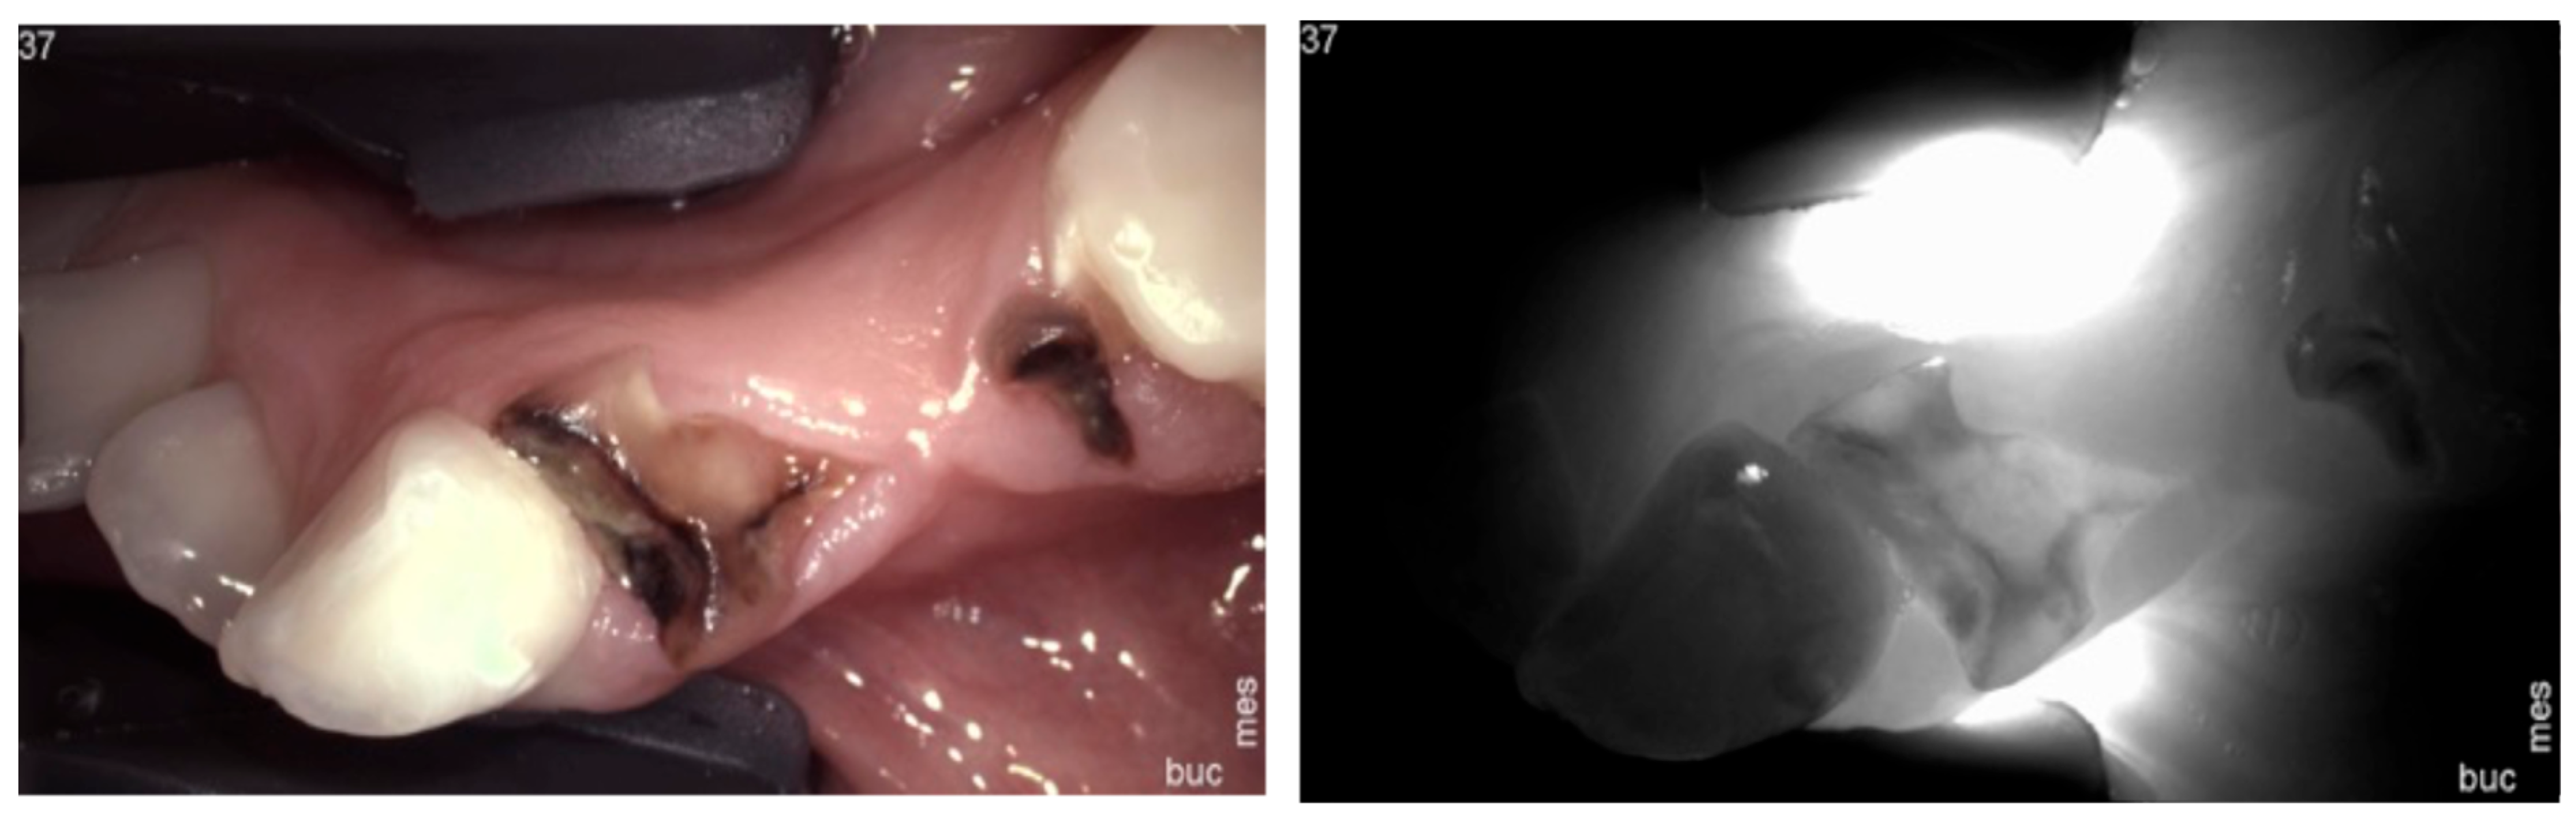

1. Healthy Teeth

2. Carious Teeth